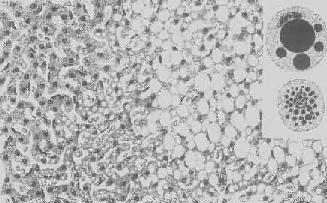

图1-17 肝细胞气球样变

病毒性肝炎时,肝细胞明显肿胀,胞浆疏松呈气球样

形态学:轻度肝脂肪变性时,肝肉眼观可无明显改变,或仅轻微黄染。如脂仿变性比较显著和广泛,则肝增大,色变黄,触之质如泥块并有油腻感。镜下,肝细胞内的脂肪空泡较小,起初多见于核的周围,以后变大,较密集散布于整个胞浆中,严重时可融合为一个大空泡,将细胞核挤向胞膜下,状似脂肪细胞(图1-18)。脂肪变性在肝小叶中的分布与其病因有一定的关系,例如肝淤血时,小叶中央区缺氧较重,故脂肪变性首先在此处发生。但长期淤血后,小叶中央区的肝细胞大多萎缩、变性或消失,于是小叶周边区肝细胞也因缺氧而发生脂肪变性。磷中毒时,肝细胞脂肪变性则主要发生于小叶周边区,这可能是由于此区肝细胞对磷中毒更为敏感的缘故。

图1-18 肝细胞脂肪变性

肝细胞胞浆内出现大小不等的脂肪空泡;右上角为饿酸染色的脂肪细胞, 脂滴染成黑色